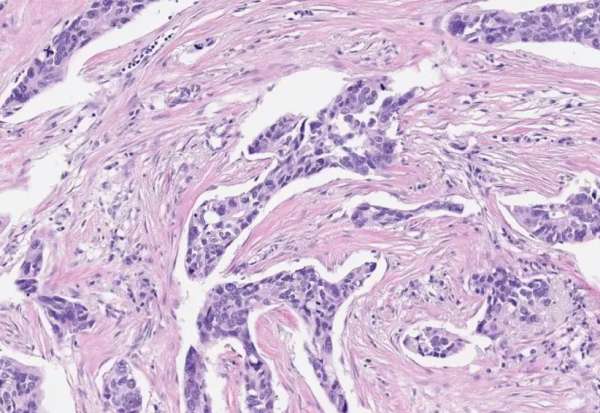

Природните антитела пронајдени во туморите би можеле да го насочат патот кон подобрена имунотерапија, според новата студија на Институтот „Вајзман“.

Новата студија спроведена во израелскиот Институт за наука „Вајзман“ ја поставува основата кон можен пробив за имунотерапија која ќе го искористи единственото оружје на имунолошкиот систем во битката со ракот: природно произведените антитела.

Во здраво тело, овој ензим налик на ножици игра важна улога во ремоделирањето на ткивата - на пример, за време на регенерација или заздравување на раните. Кај ракот дејствува во микросредината на туморот и излегува од контрола, ја пресекува матрицата околу клетките на ракот и на тој начин им помага да го нападнат околното ткиво и да се шират на другите органи, што доведува до смртоносни метастази. Истражувачите откриле дека туморите на јајчниците во нивната студија содржат ненормално високи нивоа на ензимот ММП14.

Фото: Nucleai